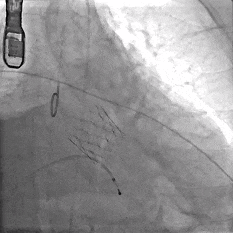

主动脉根部造影

TF29瓣膜,0位定位释放

瓣膜稳定释放至全展开

造影观察

瓣膜位置可,形态佳

左冠切线观察,瓣膜位置可,冠脉灌注良好